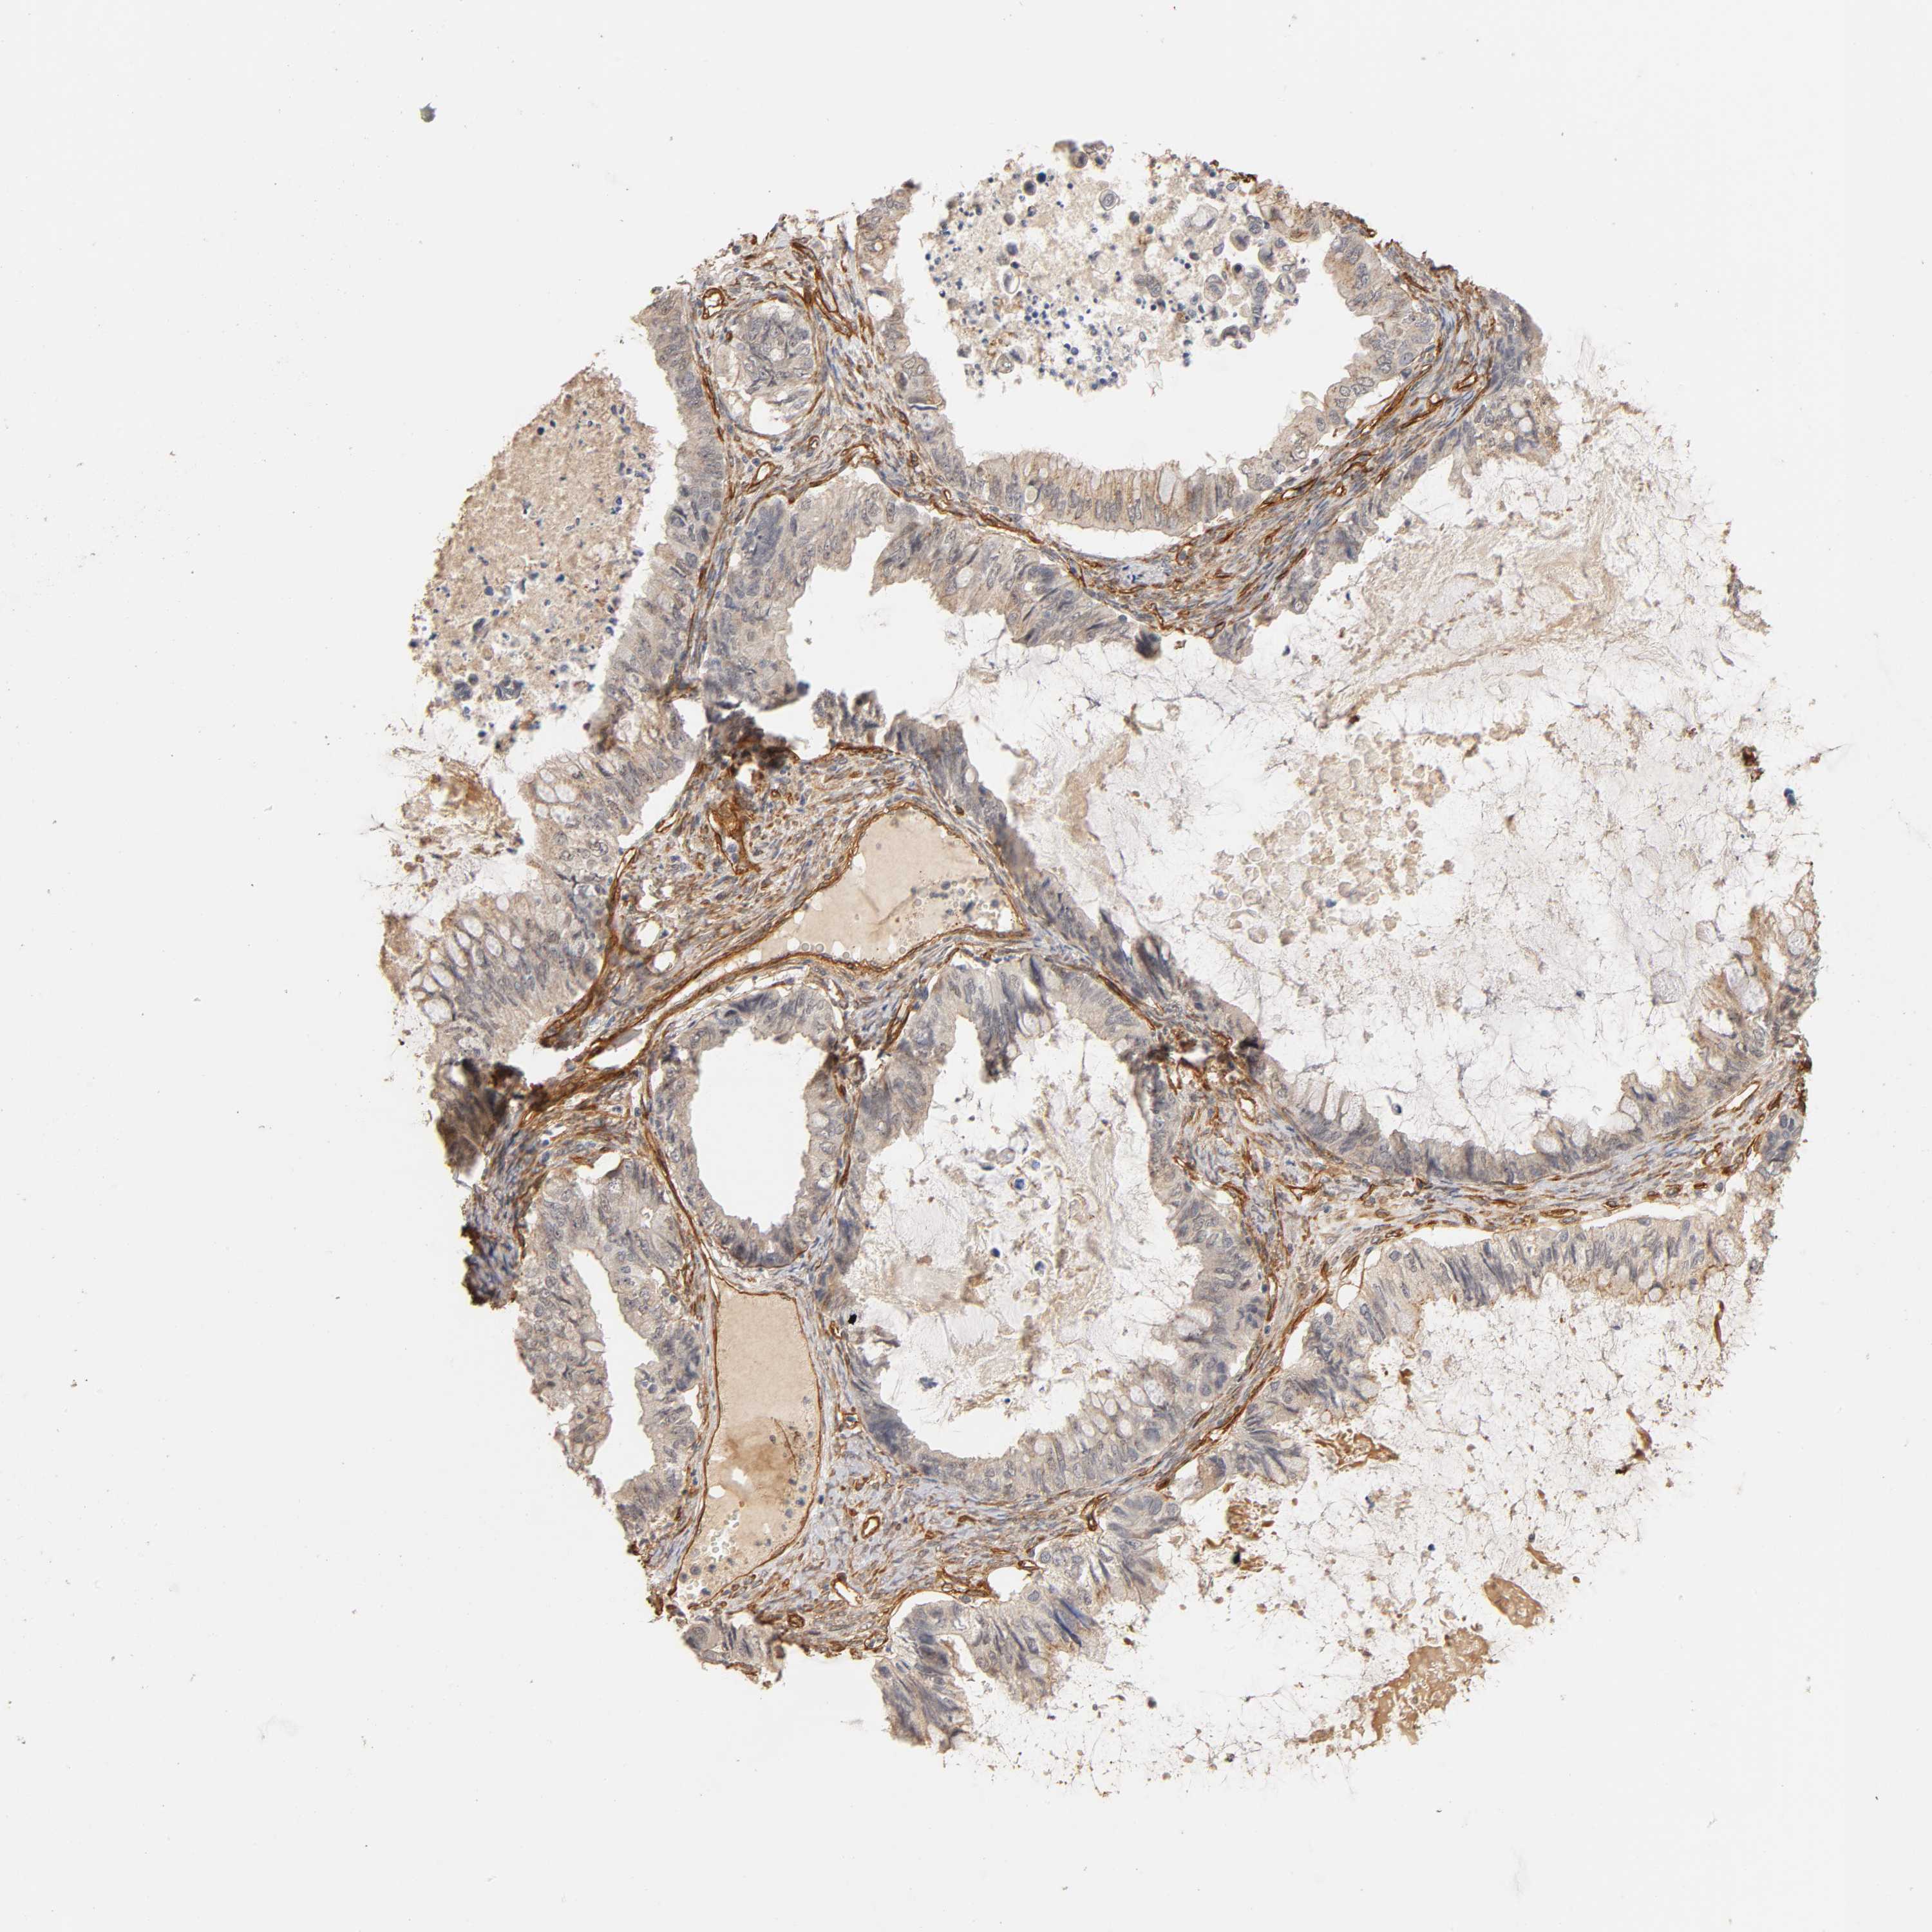

OVARIAN CANCER - Protein expressioni

A mouse-over function shows sample information and annotation data. Click on an image to view it in a full screen mode. Samples can be filtered based on level of antibody staining by selecting one or several of the following categories: high, medium, low and not detected. The assay and annotation is described here.

Note that samples used for immunohistochemistry by the Human Protein Atlas do not correspond to samples in the TCGA dataset.

Antibody stainingi

Antibody staining in the annotated cell types in the current human tissue is reported as not detected, low, medium, or high, based on conventional immunohistochemistry profiling in selected tissues. This score is based on the combination of the staining intensity and fraction of stained cells.

Each image is clickable and will lead to virtual microscopy that enables deeper exploration of all samples and also displays staining intensity scores, fraction scores and subcellular localization as well as patient and tissue information for each sample.

Antibody CAB004256

Staining

High

Medium

Low

Not detected

Carcinoma, endometroid

Cystadenocarcinoma, mucinous, NOS